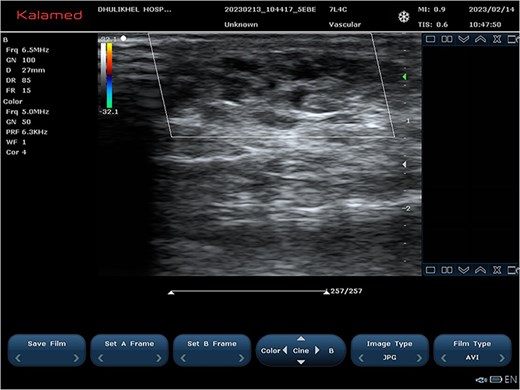

At the 2-month follow-up, significant resolution of the swelling was observed, with only minor residual fullness noted in the inframammary region of the right chest wall (Fig. 5). Ultrasonography revealed sclerosed vascular channels without flow (Fig. 6). The patient did not experience post-procedural pain. The parents were satisfied with the outcome with no residual symptomatology reported in their child since the time of the single session treatment. They ultimately opted for possible additional sclerotherapy sessions at a later date to address any residual malformation as needed.

Ultrasound images at 2-month follow-up showing sclerosed vascular channels without flow.